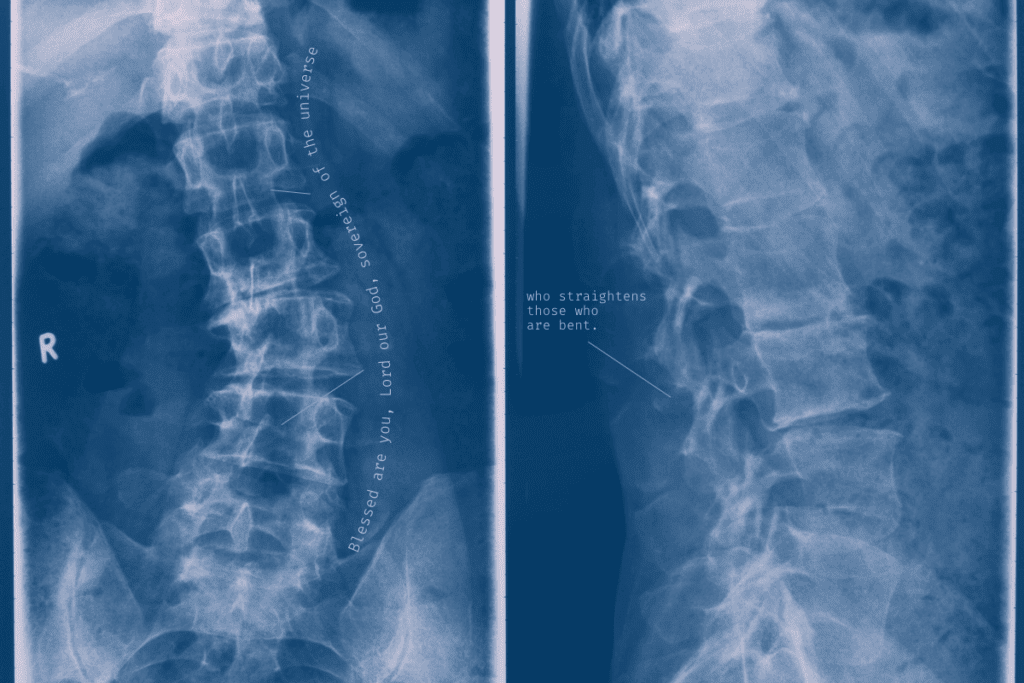

image is to be replaced’